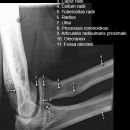

Ellenbogen ventro-dorsal (1. Ebene a.-p.)

Beurteilungskriterien

- Lage der Tuberositas radii zeigt die Stellung des Unterarms: Supination -> Tuberositas zeigt nach medial, Pronation -> Tuberositas zeigt nach lateral

- Physiologische Valgusstellung von 10 – 15°

- Ellenbogengelenkspaltweite: etwa 3mm

- Auftreten, Verschmelzung und Lokalisation der Epiphysenkerne -> Verlagerung? vgl. Anatomie Kids! Viele kindliche Verletzungen sind anhand der Verlagerung der Knochenkerne differenzierbar! Evtl. Vergleich mit Gegenseite oder MRT hilfreich.

- Target areas: Kontinuität der Knochenkontur der Fossa olecrani , der Epikondylen und Kondylen, des Olecranons.

Harmonische Darstellung des Radiusköpfchens? Impressionen? Stufe? Verdichtungen, Fissur? Knickbildung im leicht geschwungenen Radiuskopf-/Hals-Übergangs?

Cave: 50% der Radiusköpfchenfraktur sind nicht disloziert und u.U. nicht nachweisbar -> bei klinischem Verdacht ist ein positives Fettpolsterzeichen in der seitlichen Aufnahme nahezu beweisend! -> Greenspan-Aufnahme, evtl. CT oder MRT!

- Erhaltene Radius-Kapitulum-Achse? Versatz -> Luxation?

- Täuschungsmöglichkeiten: Persistierende Apophysen an Epikondylus medialis, Olecranonspitze, medialem Trochlearand oder Processus coronoideus

- Umgebende Leitungsbahnen: besonders gefährdet bei stark dislozierten Verletzungen sind der N.ulnaris (verläuft im seiner Knochenrinne durch den distalen mediodorsalen Humerus und die A.brachialis (zusammen mit N.medianus ventral des Gelenks)

- Kids: Baumannscher Winkel: Humeruslängsachse – Gerade durch die Epiphysenfuge des Capitulums ~ 70-75°. Wichtig für die Beurteilung der Repositionskontrolle nach supracondylärer Humerusfraktur